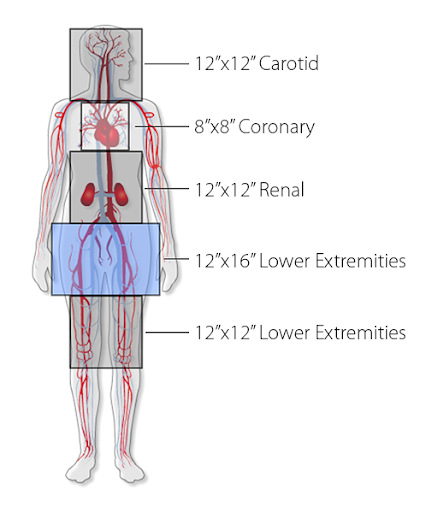

Три разных размера получаемого изображения:

-

12" x 16" - изначально предназначено для визуализации сосудов, но может быть использован и для визуализации сердца

-

12" x 12" - разработан специально для проведения различных сердечно-сосудистых диагностических и терапевтических процедур

-

8" x 8" - предназначен в первую очередь для визуализации сердца

- детекторы с возможностью получения нескольких размеров изображений в зависимости от необходимого обхема исследования. Уникальный дизайн детектора среднего (универсального - 30х30 см) размера обеспечивает в два раза большее анатомическое покрытие в одной проекции по сравнении с традиционными размерами детектора.